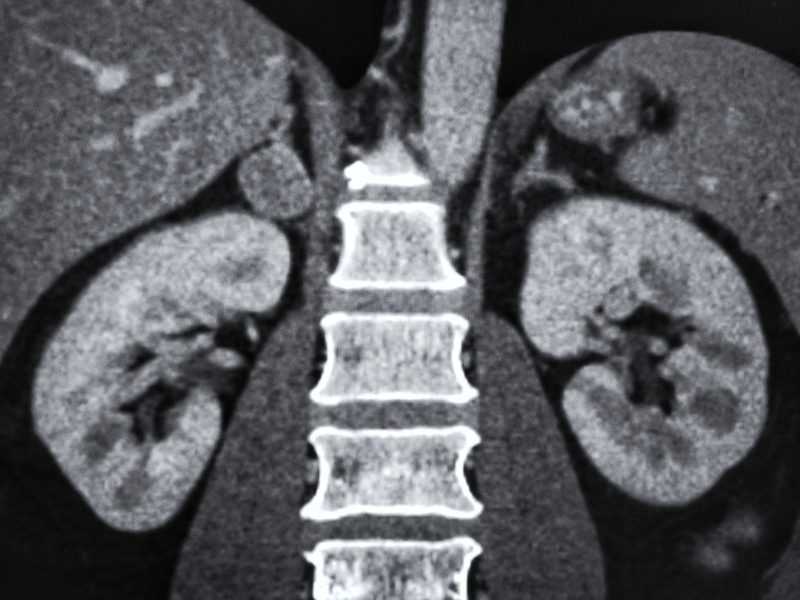

Government authorities were yet to find the exact cause of widespread kidney ailments in Supebeda's residents, though some official examinations have revealed contaminated drinking water could be one of the possible reasons. According to government authorities, an excessive content of fluoride and arsenic were reported in the groundwater of the village.